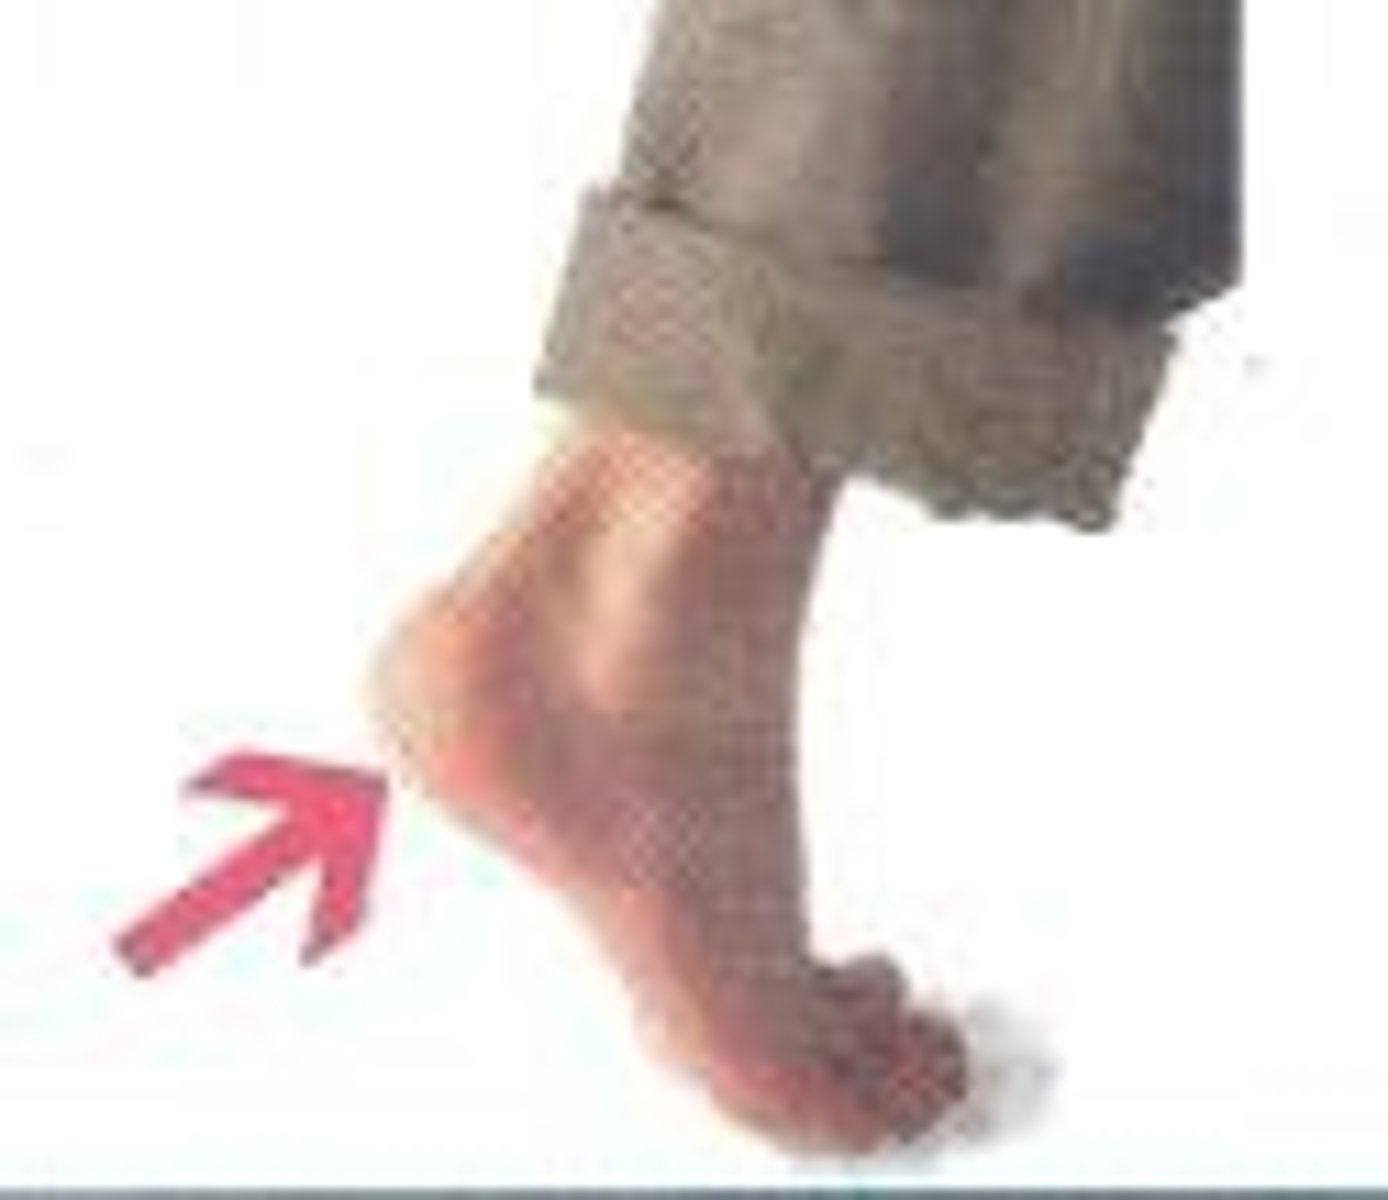

Tarsal

Ankle region

Calcaneal

pertaining to the heel